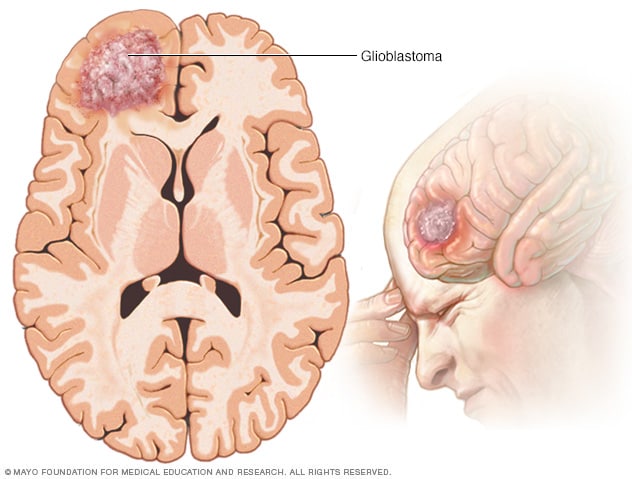

Grade 4 or glioblastoma is a very aggressive form of astrocytoma.

A new international classification system for primary brain tumors was unveiled by the World Health Organization (WHO) in 2021. This system divides astrocytomas and other types of brain tumors into many subgroups depending largely on their genetic makeup and the presence or absence of certain important changes in the tumor's specific genes. The treatment team will use information from an analysis of each tumor sample to precisely classify each tumor using the new guidelines. (Learn more about biomarker testing of the tumor in the Diagnosis section.) Key changes for the most common types of astrocytomas include:

Adult diffuse astrocytomas have now been grouped based on whether there is a mutation in the isocitrate dehydrogenase ( IDH ) gene. There are 2 groups: 1 ) astrocytoma, IDH mutant, and 2 ) glioblastoma, IDH wild-type. "Wild-type" means that the gene is found in its natural, unmutated form.

Astrocytoma, IDH mutant, can be a grade 2, grade 3, or grade 4 tumor, based on whether there are other genetic and tumor features, including a high rate of cell division (called the mitotic index) and alterations in the CDKN2A/B genes. These were previously called IDH -mutant or secondary glioblastomas.

Glioblastoma is now only used to describe IDH wild-type tumors that also have 1 or more of the following features: loss of chromosome 10, gain of chromosome 7, TERT promoter mutation, and increased number of copies of the EGFR gene. Unlike the previous classification system, glioblastomas are do not also have to show signs of cell death and excessive growth of blood vessels.

Glioblastoma

Glioblastoma is a type of cancer that starts in cells called astrocytes that support nerve cells. It can form in the brain or spinal cord.

Gliomas account for ~80% of malignant brain tumours, and the highest grade glioma, glioblastoma, is one of the most lethal cancers in adults 3 . Interestingly, genomic sequencing efforts more than 10 years ago jump-started the field of glioma metabolism with their finding of recurrent mutations in the genes encoding the tricarboxylic acid cycle enzymes IDH1 and IDH2, but the role of metabolism in glioma pathogenesis goes beyond IDH, as discussed by Bi et al. 7 .